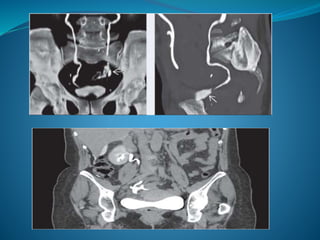

 Extravasation of contrast material in computed

tomography (CT) is the hallmark sign of ureteral

trauma.

Diagnostic evaluation  Ahigh index of suspicion of ureteral injury should be maintained as the majority of cases are diagnosed late, predisposing the patient to pain, infection, and renal function impairment.  Haematuria is an unreliable indicator.  Extravasation of contrast material in computed tomography (CT) is the hallmark sign of ureteral trauma.  In unclear cases, a retrograde or antegrade urography is required for confirmation